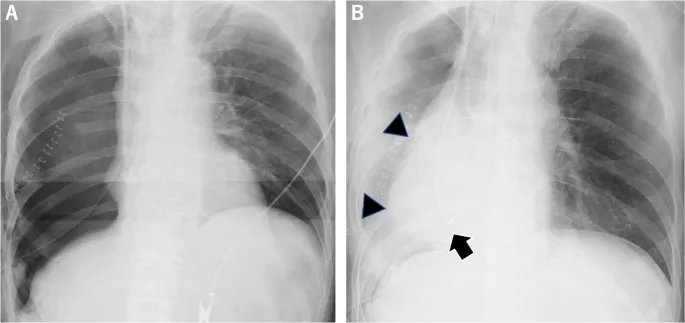

- CXR shows opacification and volume loss.

- Hallmarks: Refractory hypoxemia and bilateral pulmonary infiltrates on CXR, not due to heart failure.